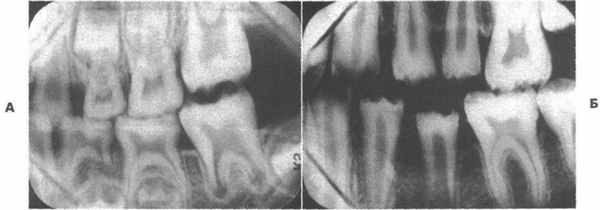

Рентгенологические признаки:

- уменьшение зон роста – вместо дуги заметна прямая линия на краю ростковой зоны;

- псевдотауродантизм – увеличенное расстояние от окклюзивной поверхности коронки моляра до зоны бифуркации при хорошо заметной облитерированной полости зуба;

- недоразвитые корни с заостренными верхушками;

- в молочных зубах – полная облитерация полостей;

- в коренных – бывает атипичная форма зубной полости;

- часто видны очаги разрежения с обрывчатыми границами вокруг корней;

- вершины межальвеолярных перегородок находятся ниже эмалево-цементного соединения.

Дисплазия — редкое нарушение формирования дентина. Shields, Bixler и El-Kafrawy выделили два типа данной аномалии: дисплазия радикулярного дентина (тип I) и дисплазия коронкового дентина (тип II). I тип наследуется аутосомно-доминантно, при этом могут поражаться как молочные, так и постоянные зубы. На рентгенограммах видны короткие заостренные корни; корневые каналы и пульпарная камера обычно отсутствуют, за исключением шарообразных остатков в коронковой части. Цвет и форма коронок таких зубов обычно не изменены, хотя иногда зубы выглядят слегка опалесцентными и голубоватыми.